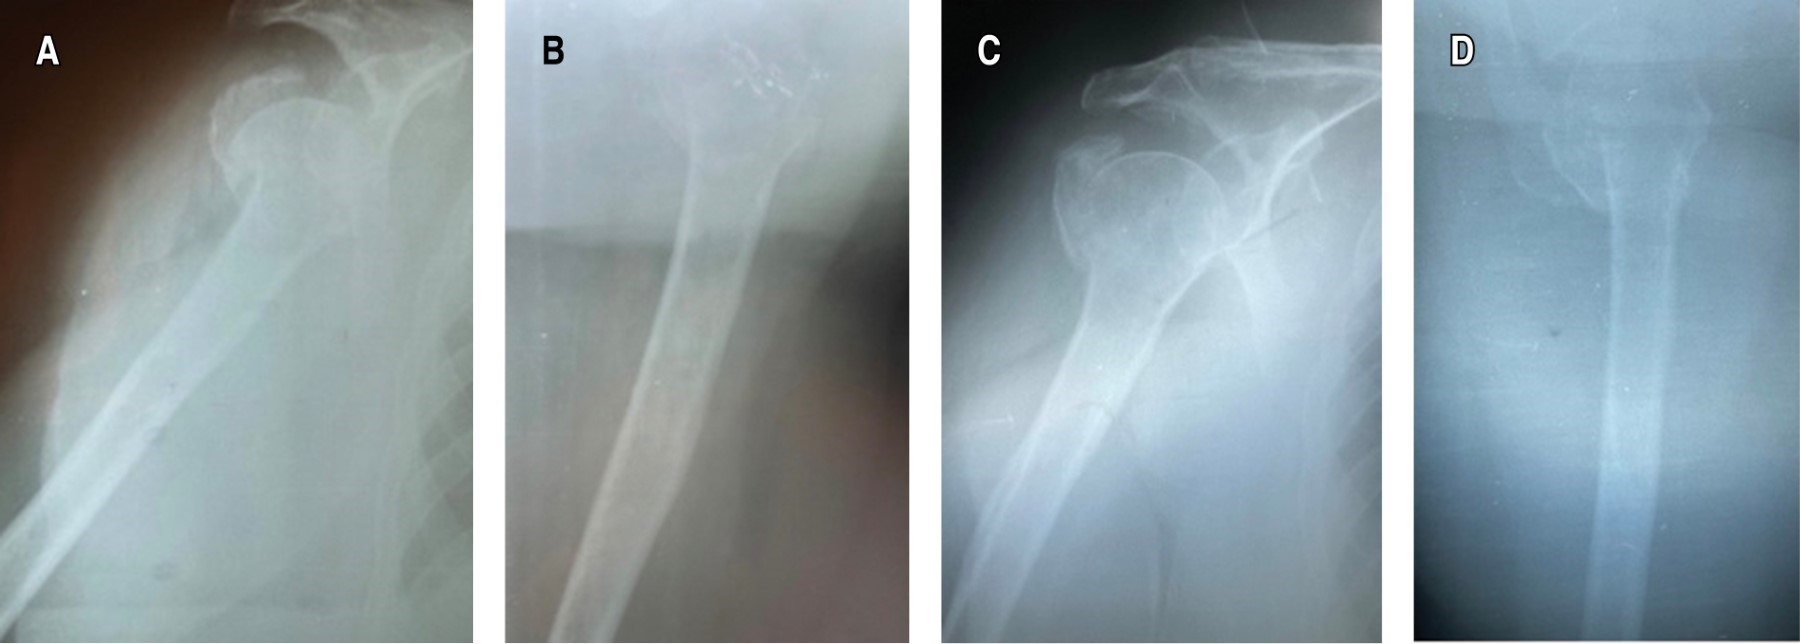

Early mobilization in the conservative management of proximal humeral fractures. A real risk?

Early mobilization is the mainstay of conservative management of proximal humerus factures. In Mexico, the immobilization time is usually 3-4 weeks, followed by rehabilitation process, for fear of the risk of complications such as non-union, despite the fact that research supports early mobilization for a better patient prognosis. Objective: To determine if early mobilization, on the seventh day of immobilization, brings radiological bone consolidation and early positive functional results in Mexican patients with Neer II proximal humerus fracture. Material and methods: This is a prospective case report of 3 patients > 50 years with a diagnosis of Neer II proximal humerus fracture, they were immobilized for seven days with subsequent early mobilization, the Constant-Murley Functional Scale, DASH Questionnaire, and Montoya radiological scale at the first, second and third month of evolution. Results: Patient 1. First month Constant Murley 26, DASH 64.1, Montoya GII, second month Constant-Murley 67.35, DASH 32.5, Montoya GIII, third month Constant-Murley 98, DASH 2.5, Montoya GIV. Patient 2. First Month Constant-Murley 44, DASH 33.3, Montoya GII, second month Constant-Murley 59.35, DASH 39.16, Montoya GIII, third month Constant-Murley 94, DASH 4, Montoya GIV. Patient 3. First month Constant-Murley 38, DASH 57.5, Montoya GII, second month Constant-Murley 67.62, DASH 10.83, Montoya GIII, third month Constant-Murley 96, DASH 5.75, Montoya GIV. Conclusion: Early mobilization in Mexican patients with Neer II proximal humerus fracture brings early excellent radiological and functional results if the patient is followed appropriately.

Figure 3

Figure 4

Figure 5

Figure 6

Figure 7

Figure 8

Figure 9

Figure 10